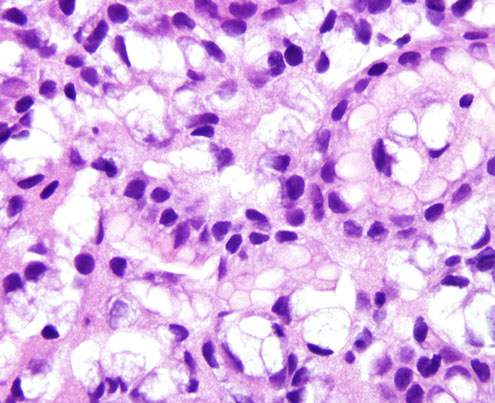

Gastric MALT lymphoma

LG B-cell lymphoma of Mucosa-Assoc Lymphoid Tissue (MALT); may be called extranodal marginal zone lymphoma

90% assoc c H pylori

30% plasmacytic differentiation

Micro: at low power, lamina propria expanded c small uniform cells, some of which have a "halo" around

- should start to assess muscularis mucosae, which usually have infiltrates of cancer cells

- the "lymphoepithelial" lesion (LEL) has lymphs scattered in residual gland epithelium (but not always there)

IHC: (+) CD20/79a, BCL2, IgM, can have plasmacytoid differentiation c Ig LC restriction; should assess for H pylori

- variable CD11c/43

- neg CD5/10/23

may assess for CD20 reactive B cells that aberrantly express CD43; should also compare cells that may coexpress CD3 and CD43 (which is normal)

Genes: all translocations 2/2 pathway assoc c nuclear factor kappaLC enhancer of activated B cells (NFkB)

t(11:18)(q21;q21), API2/MALT1 in up to 1/3; not assoc c H pylori infx (thus do not respond to abc tx); but does have nuclear BCL10 expression

- also t(1;14)(p22;q32) IGH-BCL10, t(14;18)(q32;q21) IGH-MALT1; and t(3;14)(p14;q32) IGH-FOXP1

-- note the q32 located on the cr14; q21 for cr18

DDx: lots of plasma cells usually seen in reactive lesions (H pylori gastritis)

- other large B cell gastric lymphomas c large-cell rich infiltrat, should run flow, stain for CD117 / c-kit, CD20/3, and keratins, and S100, CD30

Tx: 50% will not improve c treatment of underlying H pylori

- posttreatment histo grading system based on eval of lymphoid infiltrate, LEL presence, and stromal changes

can grade as "Complete Histological Response (CR)", "Probable minimal residual dz (pMRD)", "Responding Residual Dz (r-RD)" and "No Change (NC)"

- rRD implies lymphoma is present, but also has features to suggest that it is responding, which means to stay on current tx

Px: can induce long-term remission in 4/5 cases

- LG lymphomas can infrequently appear c tx of H pylori, but they spontaneously regress

Gastric MALT lymphoma

Lymphoepithelial lesion